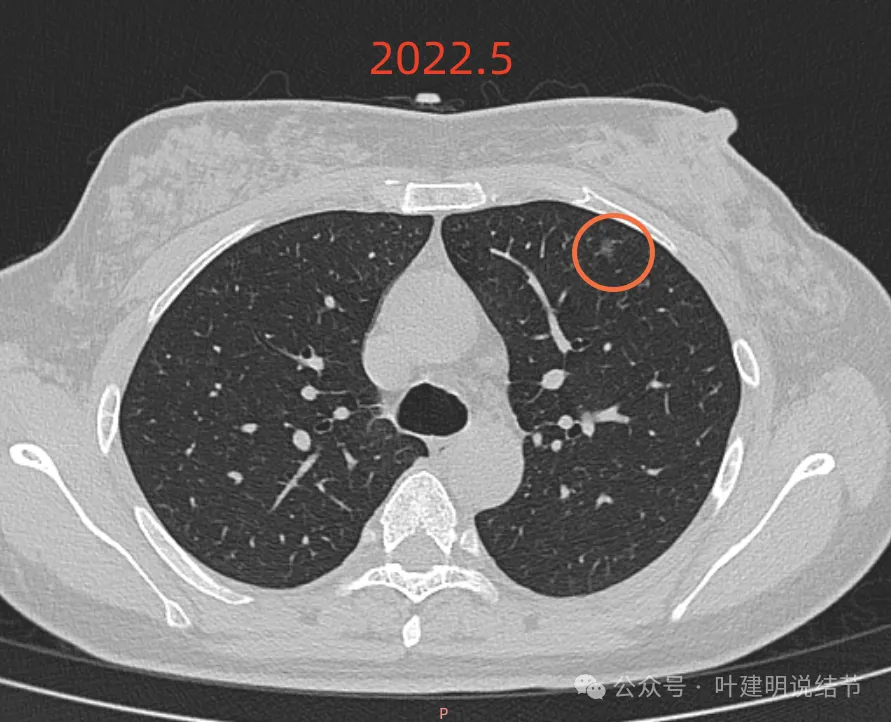

再看2022年5月时的影像:

这时B医院医生主张手术时的情况:

三处病灶均仍在,间隔3个月显然说不上明显进展或变化。这时候问诊我,我对比后认为风险仍低,能再随访,结友停掉了本已经预约的手术。